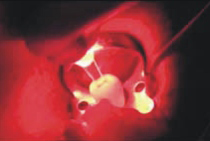

FotoSan 360

Přístroj na principu světlem aktivovaná desinfekce neboli fotodynamická antimikrobiální chemoterapie. Přístroj s okamžitým účinkem ničí veškeré mikroorganismy bez jakýchkoli vedlejších účinků. Jedná se o bezbolestné ošetření, které nevyžaduje anestezii, nemá vedlejší účinky a ničí 99% bakterií. Používá se především v parodontologii a implantologii při léčbě zánětů v okolí zubů a implantátů (dezinfekce tzv. chobotů), záchovné stomatologii (ošetření kazů) i endodoncii (dezinfekce kanálků zubu).